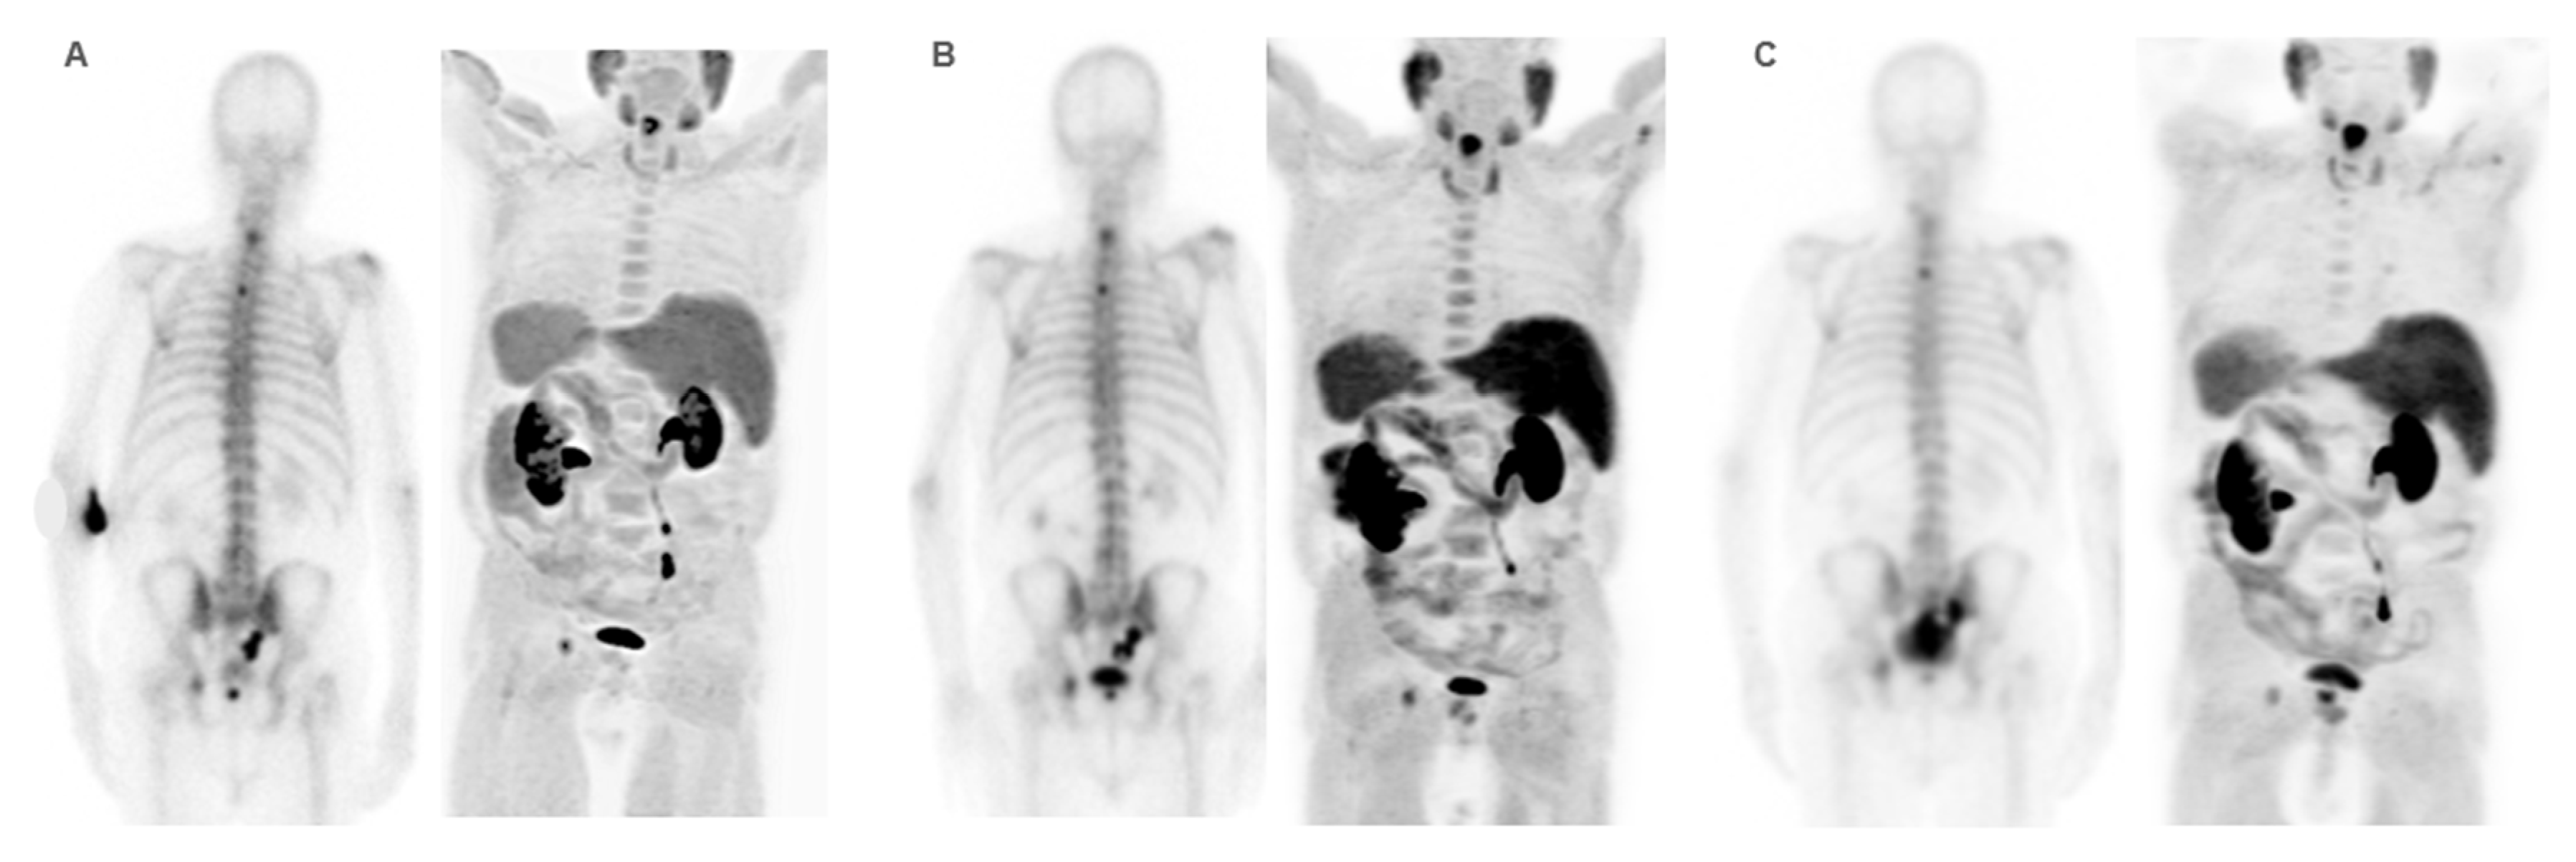

Diagnostic Imaging in Patient Selection

Response Assessment

Skeletal Events